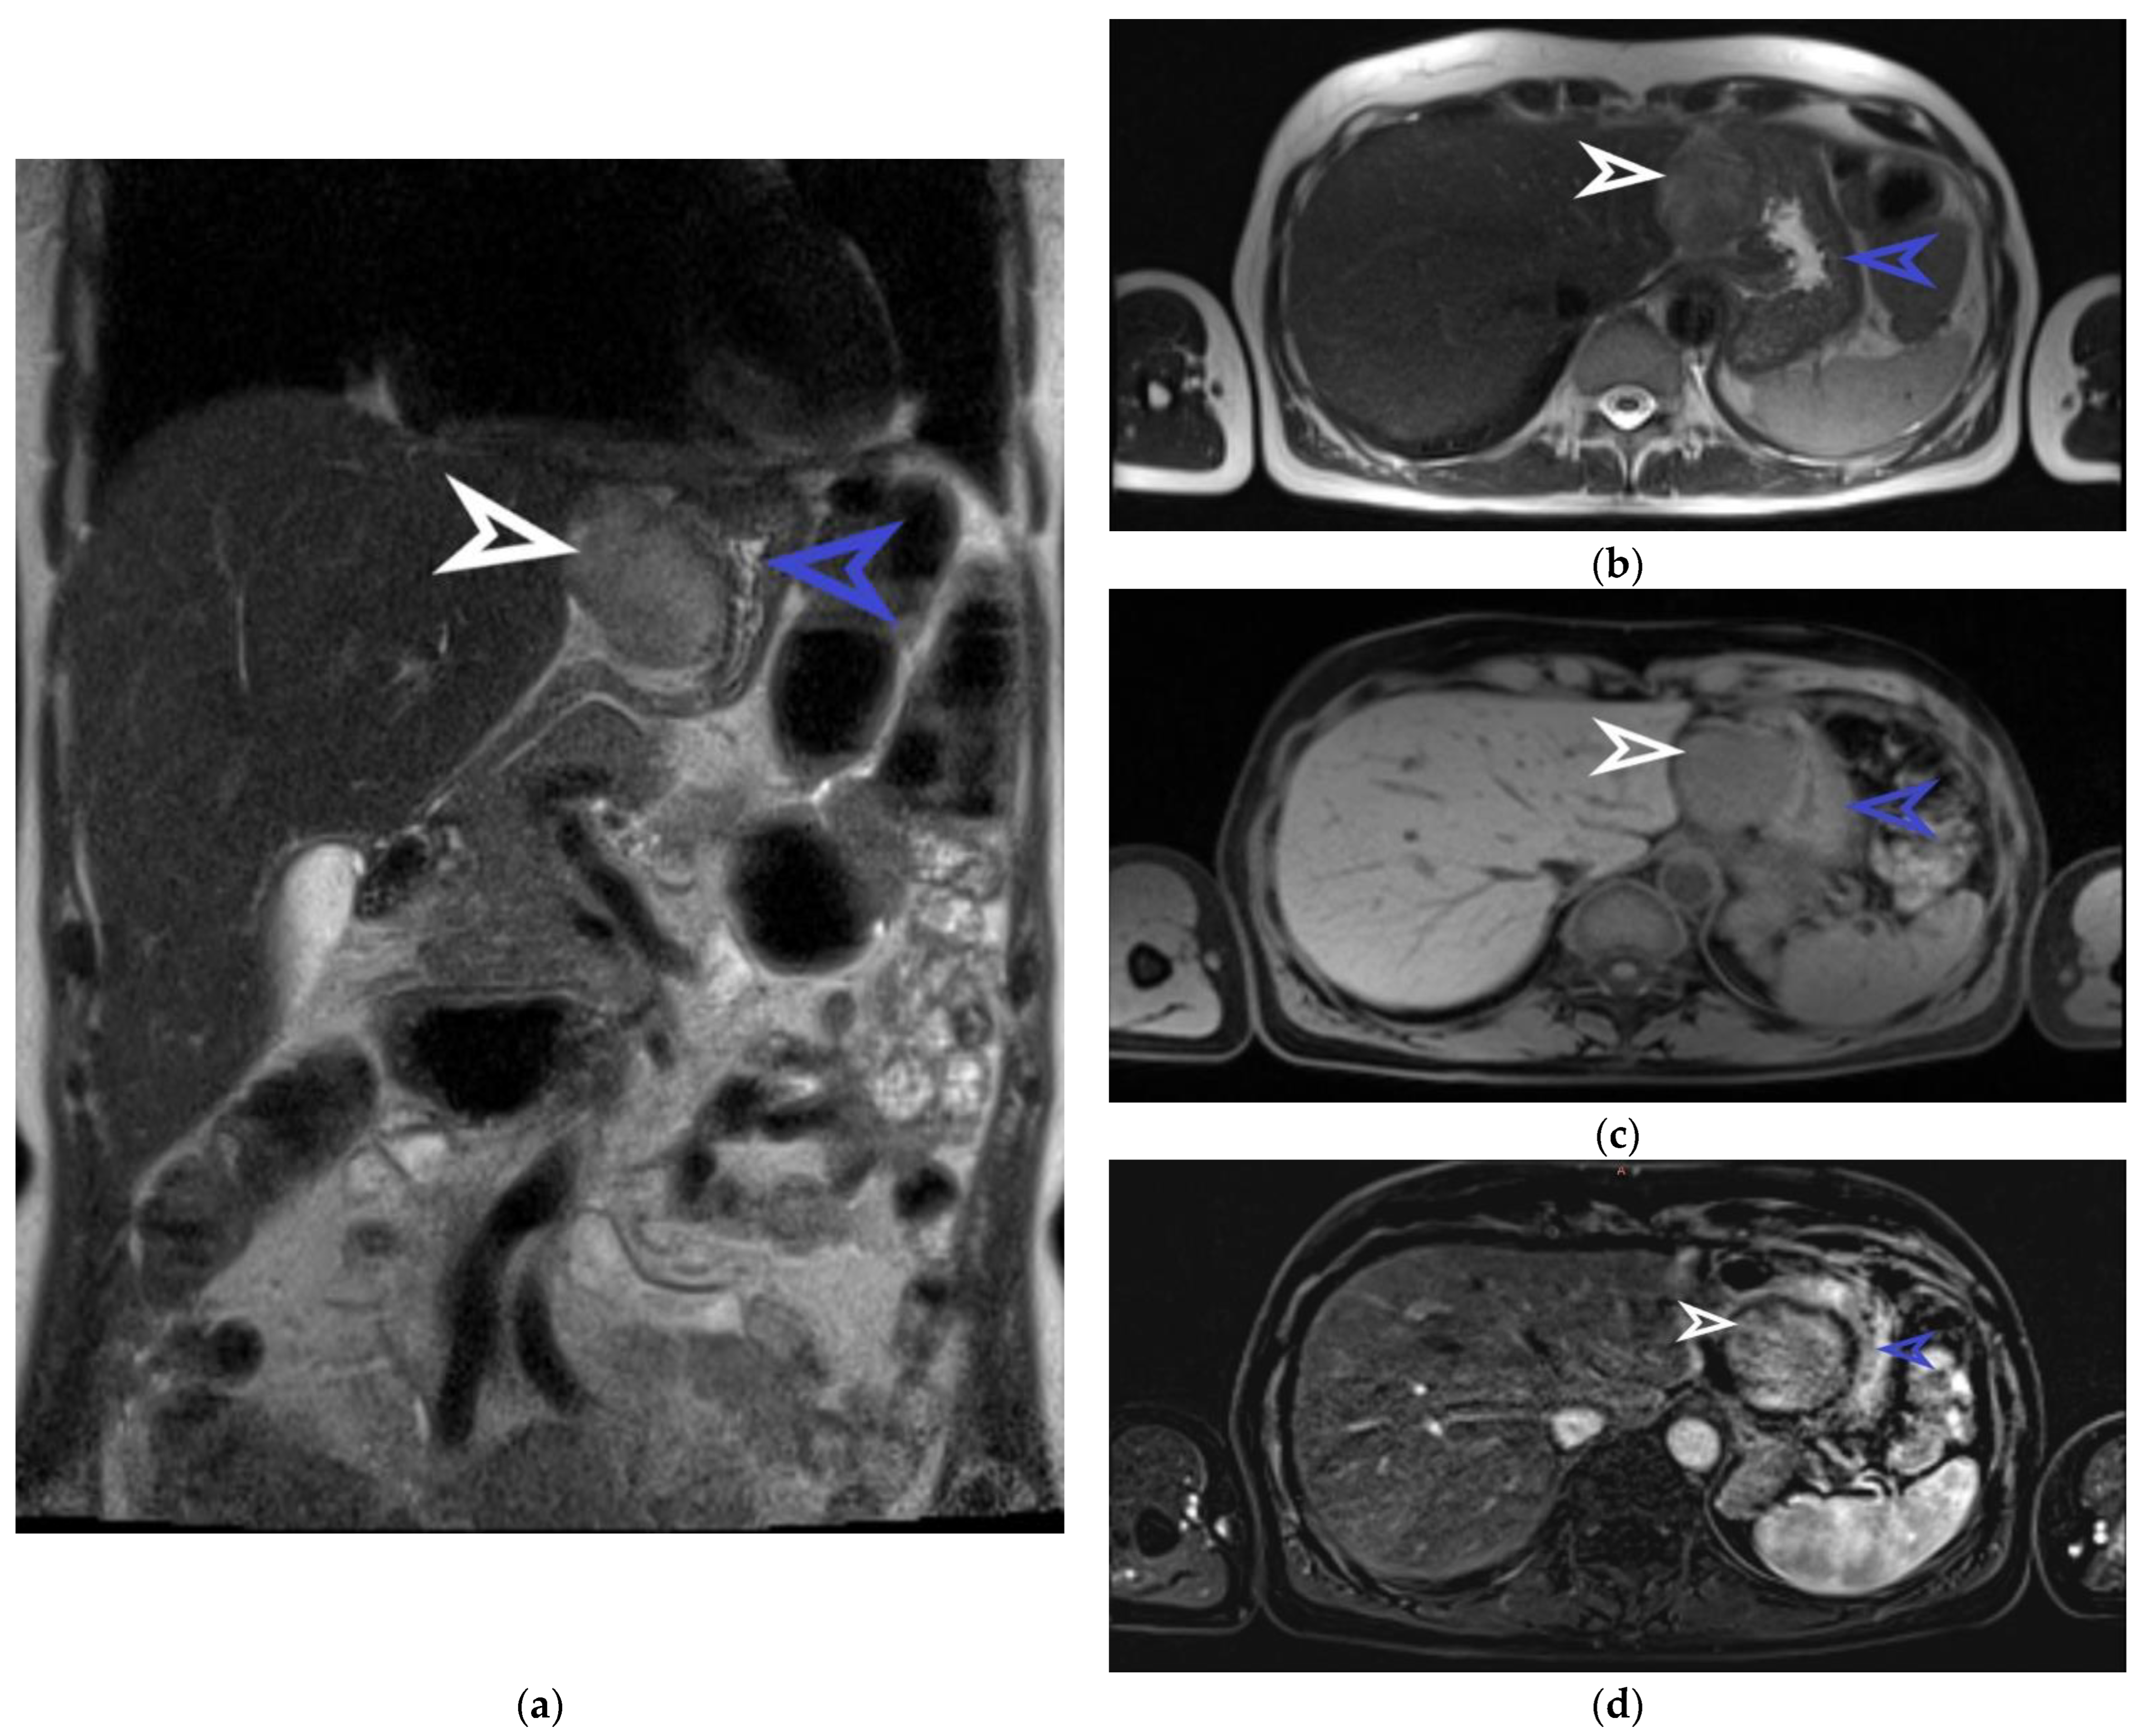

Abdominal MRI examination, coronal section. The well-defined tumor originating from the anterior gastric wall with a heterogeneous T2 intermediate signal is marked with a white arrow. The stomach is indicated by the blue arrow (a). Abdominal MRI examination, transverse section, and T2 sequence. The tumor is marked with a white arrow and the stomach is marked with a blue arrow (b). Abdominal MRI examination, transverse section, and T1 sequence. The tumor is indicated by the white arrow and the stomach is indicated by the blue arrow (c). Abdominal MRI examination, transverse section, and T1 arterial sequence. The tumor is marked with a white arrow and is shown to have a hypo-signal T1, gadofil, and slightly restricted diffusion. The blue arrow indicates the stomach (d). The patient was examined and treated in the Brașov County Emergency Clinical Hospital and in the Emergency Hospital of Craiova between November and December 2022. She is not on any medication at present nor on any proton pump inhibitors. She has been in menopause for a couple of years, had 2 natural births, and had her first menstruation at the age of 15. The laboratory exams did not reveal any pathological changes, as she had a hemoglobin value of 14.8 g/dL, red blood cells 5 × 106/uL, white blood cells 6.54 × 103, INR 1.01, APTT 21.7 sec, urea 43 mg/dL, and creatinine 0.86 mg/dL. The patient later underwent an abdominal MRI for the characterization and determination of the tumor’s origin. This imaging examination described the tumor detected by ultrasound as round-oval. It was found to have an exophytic growth from the gastric wall, dimensions of 44/50 mm, an intermediate heterogeneous T2/T2 FS signal, hyposemnal T1, to be gadophilic, and to overall be slightly restricted in diffusion. Figure 2 captures some suggestive images of the tumor’s appearance on the MRI.